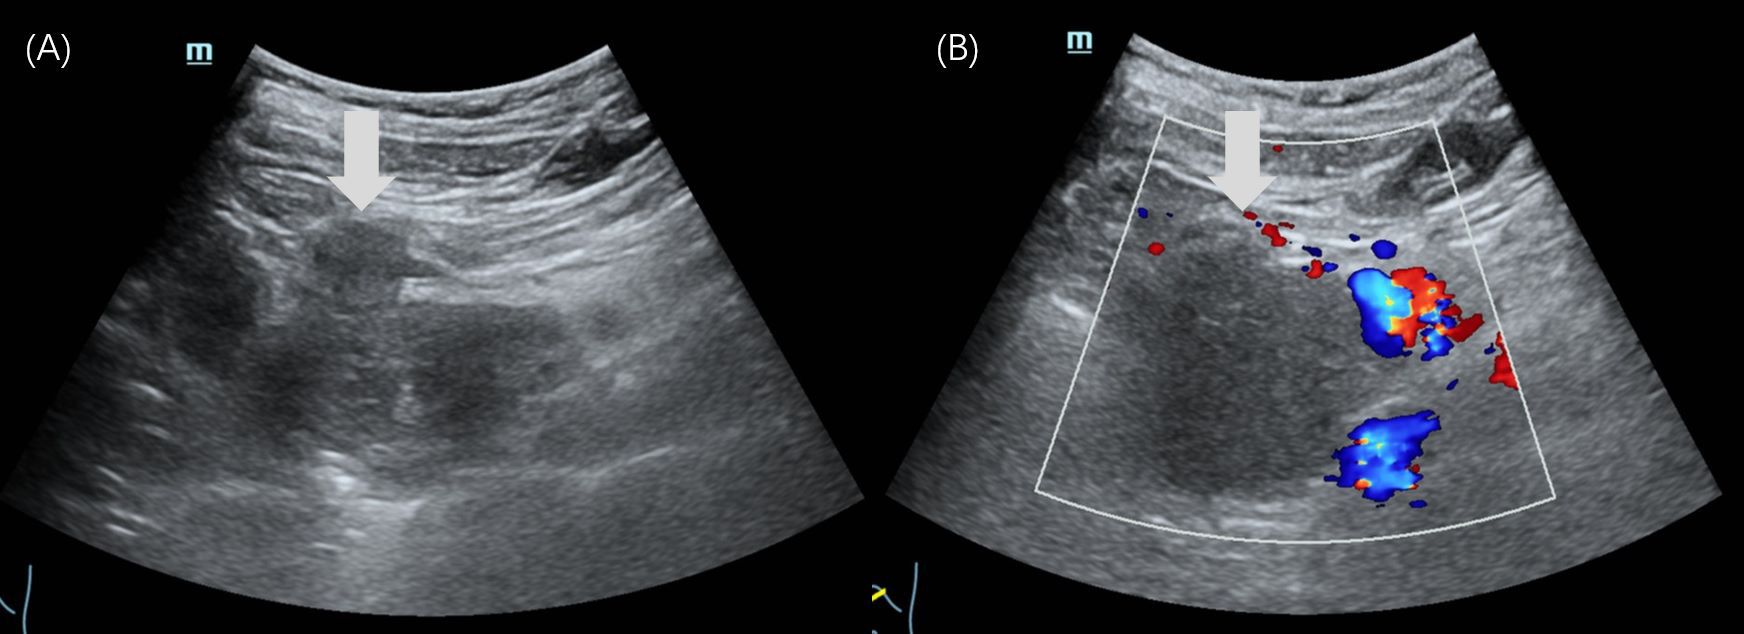

Pancreatoblastoma (PB) is a rare malignant neoplasm of the pancreas, primarily affecting children. While some reports have described the imaging characteristics of PB, detailed descriptions of its ultrasound (US) and contrast-enhanced ultrasound (CEUS) features in children are limited. We reported two cases of PB admitted to our hospital with detailed ultrasonographic features. The first case involved a 14-year-old girl who presented with intermittent, unexplained epigastric pain. CEUS revealed a hypoechoic mass with heterogeneous hyperenhancement in the pancreatic head. She underwent pancreaticoduodenectomy and remains disease-free to date. The second case was a 4-year-old boy with a palpable, unexplained mass in the right upper abdomen. US identified a well-defined, heterogeneous mass in the epigastric region with internal point-like hyperechoic areas. The intraoperative US showed portal vein cancer thrombus. He underwent tumor resection along with reconstruction of the portal and superior mesenteric veins. He subsequently received chemotherapy and remained disease-free to date.